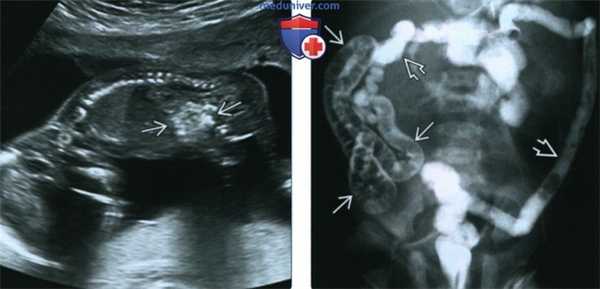

(Слева) УЗИ плода в 17 нед., сагиттальная плоскость. Определяются гиперэхогенные петли кишечника («яркие, как кость»). В случае выявления необходимо исключить все причины гиперэхогенности кишечника, включая муковисцидоз (МВ), анеуплоидию, инфицирование, пороки развития кишечника и кровотечение в анамнезе (заглатывание крови).

(Справа) Препятствием для прохождения контрастного вещества в данном случае является меконий. Определяются микроколон, а также многочисленные дефекты наполнения из-за скопления мекония в дистальном участке подвздошной кишки. Данная картина характерна для мекониевого илеуса при муковисцидозе (МВ). (Слева) УЗИ плода в 33 нед. Расчетный риск муковисцидоза (МВ) - 25%. Определяются незначительный асцит и умеренно гиперэхогенные петли кишечника.

(Справа) Препятствием для прохождения контрастного вещества в данном случае является меконий. Определяются микроколон, а также многочисленные дефекты наполнения из-за скопления мекония в дистальном участке подвздошной кишки. Данная картина характерна для мекониевого илеуса при муковисцидозе (МВ).